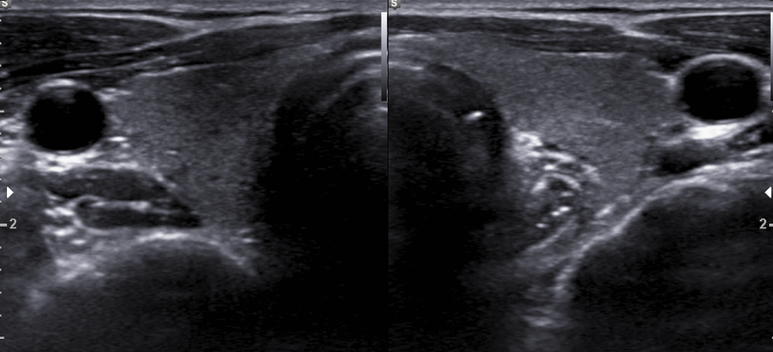

2014년 후반 갑상선

area VI 에 LN로 생각되는 결절

3개월뒤 추적 검사

갑상선 실질이 거칠어지고 저음영의 미세결절들이 증가되어 관찰